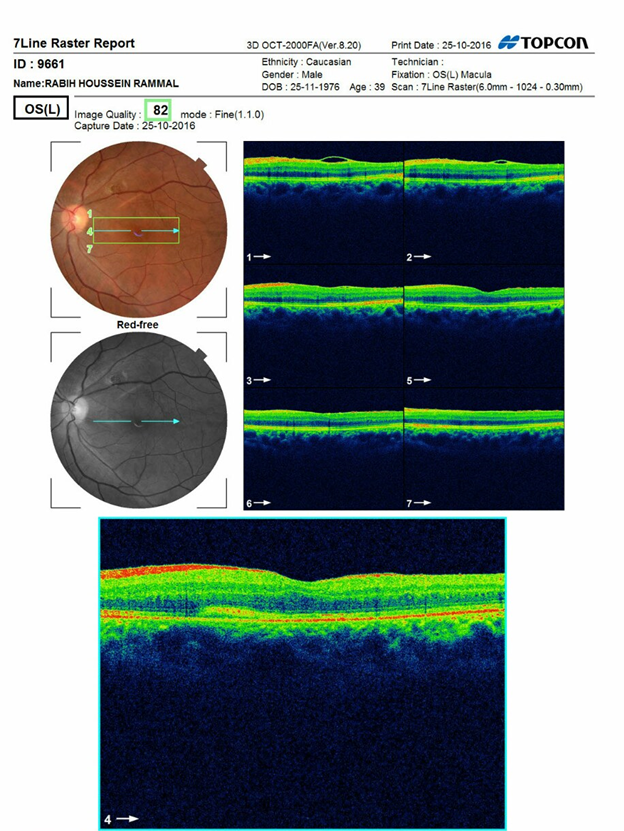

Pre operation fundus photo and OCT of left eye

Figure 1

Figure 2